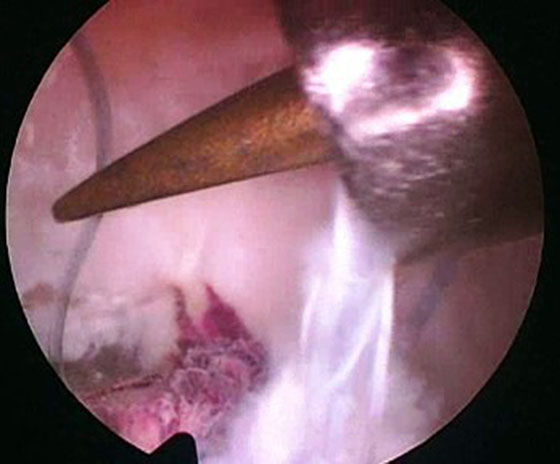

Se procede luego a realizar el portal posterointerno. Dado que no se reseca el remanente HPM, el espacio para acceder a la cápsula posterointerna se encuentra reducido, para ampliarlo realizamos una mínima “notchplastia” en la parte posterior del cóndilo interno (Fig. 4). Con la visión desde el portal anterointerno colocamos un switcher, de los utilizados en cirugía de hombro, desde el portal anterolateral ubicándolo entre el remanente ligamentario y el cóndilo interno (Fig. 5). Luego se pasa la cánula de irrigación guiada por el switcher y se accede con la óptica a la cápsula posterointerna, bajo visión directa colocamos una aguja espinal para localizar el portal, completando con bisturí para luego colocar la cánula de trabajo (Fig. 6). En este punto se vuelve a pasar el artroscopio al portal anterointerno, se introduce el shaver por la cánula del portal posterointerno, y se realiza la limpieza de la capsula posterior, siempre con la hoja de corte hacia anterior para evitar la lesión de estructuras vasculonerviosas. Se continúa alternando los portales anterointerno y posterointerno con visión, shaver, pinza basket y raspas de 90º, hasta completar la desinserción de cápsula posterior e identificar el remanente distal del ligamento sin afectar la inserción. En los casos en que la lesión ha sido en la sustancia colocamos la guía tibial distal a la inserción tibial (Fig. 7). Si la lesión ha comprometido la inserción tibial, levantamos la cicatriz que encontremos y colocamos la guía por debajo del remanente (Fig. 8). Para la introducción de la guía sin lesionar los remanentes ni el LCA se coloca la óptica en el portal anteroexterno y se controla el ingreso de la guía por el espacio entre el remanente y el cóndilo interno (Fig. 9). Se pasa el clavo guía, siempre cuidando de llegar en forma motorizada hasta contactar la cortical posterior y se completa el pasaje golpeando con martillo para evitar una salida brusca del mismo. Se pasa la fresa canulada del diámetro adecuado, protegiendo la emergencia de la misma con una cureta. Una vez completado el túnel tibial, se pasa un alambre o cable desde el orificio externo tibial hacia proximal, con visión en portal posterointerno, al ver emerger el alambre o cable por el orificio tibial posterior, se vuelve la óptica al portal anterointerno para controlar el pasaje de un grasper desde anteroexterno a través del intervalo entre HAL y LCA, y dirigirlo hacia posterior (Fig. 10); se vuelve con la óptica al portal posterointerno y se visualiza la recuperación del alambre o cable con el grasper hacia la parte anterior de la rodilla (Fig. 11). Se amplía el portal anteroexterno y se anuda la sutura tractora del injerto al alambre o cable, y traccionando desde el orificio distal del túnel tibial se hace ingresar el injerto en forma retrógrada a la articulación y, luego, al túnel tibial por su orificio posterior. En caso que se utilice el injerto de tendón cuadricipital la parte tendinosa irá al túnel tibial y el bloque óseo al femoral. Una vez ingresado el injerto al túnel tibial, se vuelve la óptica al portal anterointerno, en el portal anteroexterno tendremos la sutura tractora del extremo “femoral del injerto”, es aconsejable en este punto llevar el injerto lo más distal posible para tener mejor visión articular, enhebrar la sutura tractora en una cánula de unos 6 mm de diámetro, para asegurarse que la sutura tractora y la clavija pasasutura pasan por el mismo espacio sin incluir tejido sinovial o grasa retrorrotuliana (Fig. 12). Se procede a pasar la aguja pasasutura por el túnel femoral, saliendo por las partes blandas de la parte medial de la rodilla, se tracciona y se asciende el injerto colocándolo en el túnel femoral. En caso que el injerto tenga bloque óseo puede ser necesario redirigir el mismo para ubicarlo en el túnel femoral, para esto ubicamos la visión en el portal anteroexterno y por el portal anterointerno utilizamos el trocar romo o el palpador para realizar una polea y mejorar la tracción para que ingrese el taco óseo en el túnel femoral (Fig. 13). Luego se realiza la fijación femoral con tornillo de interferencia de titanio o biodegradable. A continuación liberamos el manguito neumático, porque creemos que produce un espasmo en los isquiotibiales que dificulta la reducción de la tibia, dejamos pasar unos minutos que utilizamos para colocar un tornillo maleolar con arandela, distal al orificio externo del túnel tibial para realizar una segunda fijación de la parte tibial. Preferimos hacerlo antes de colocar el tornillo interferencial, porque esto generará una presión hacia posterior de la tibia. Se realiza la reducción tibial en 90° de flexión de la rodilla, se tracciona del injerto y se coloca el tornillo de interferencia tibial, luego la sutura remanente (polyester 5) se anuda en el tornillo maleolar completando la 2da fijación. Por último se constata con una nueva visión articular la posición y tensión del injerto (Fig. 14).

Figura 10

Figura 11